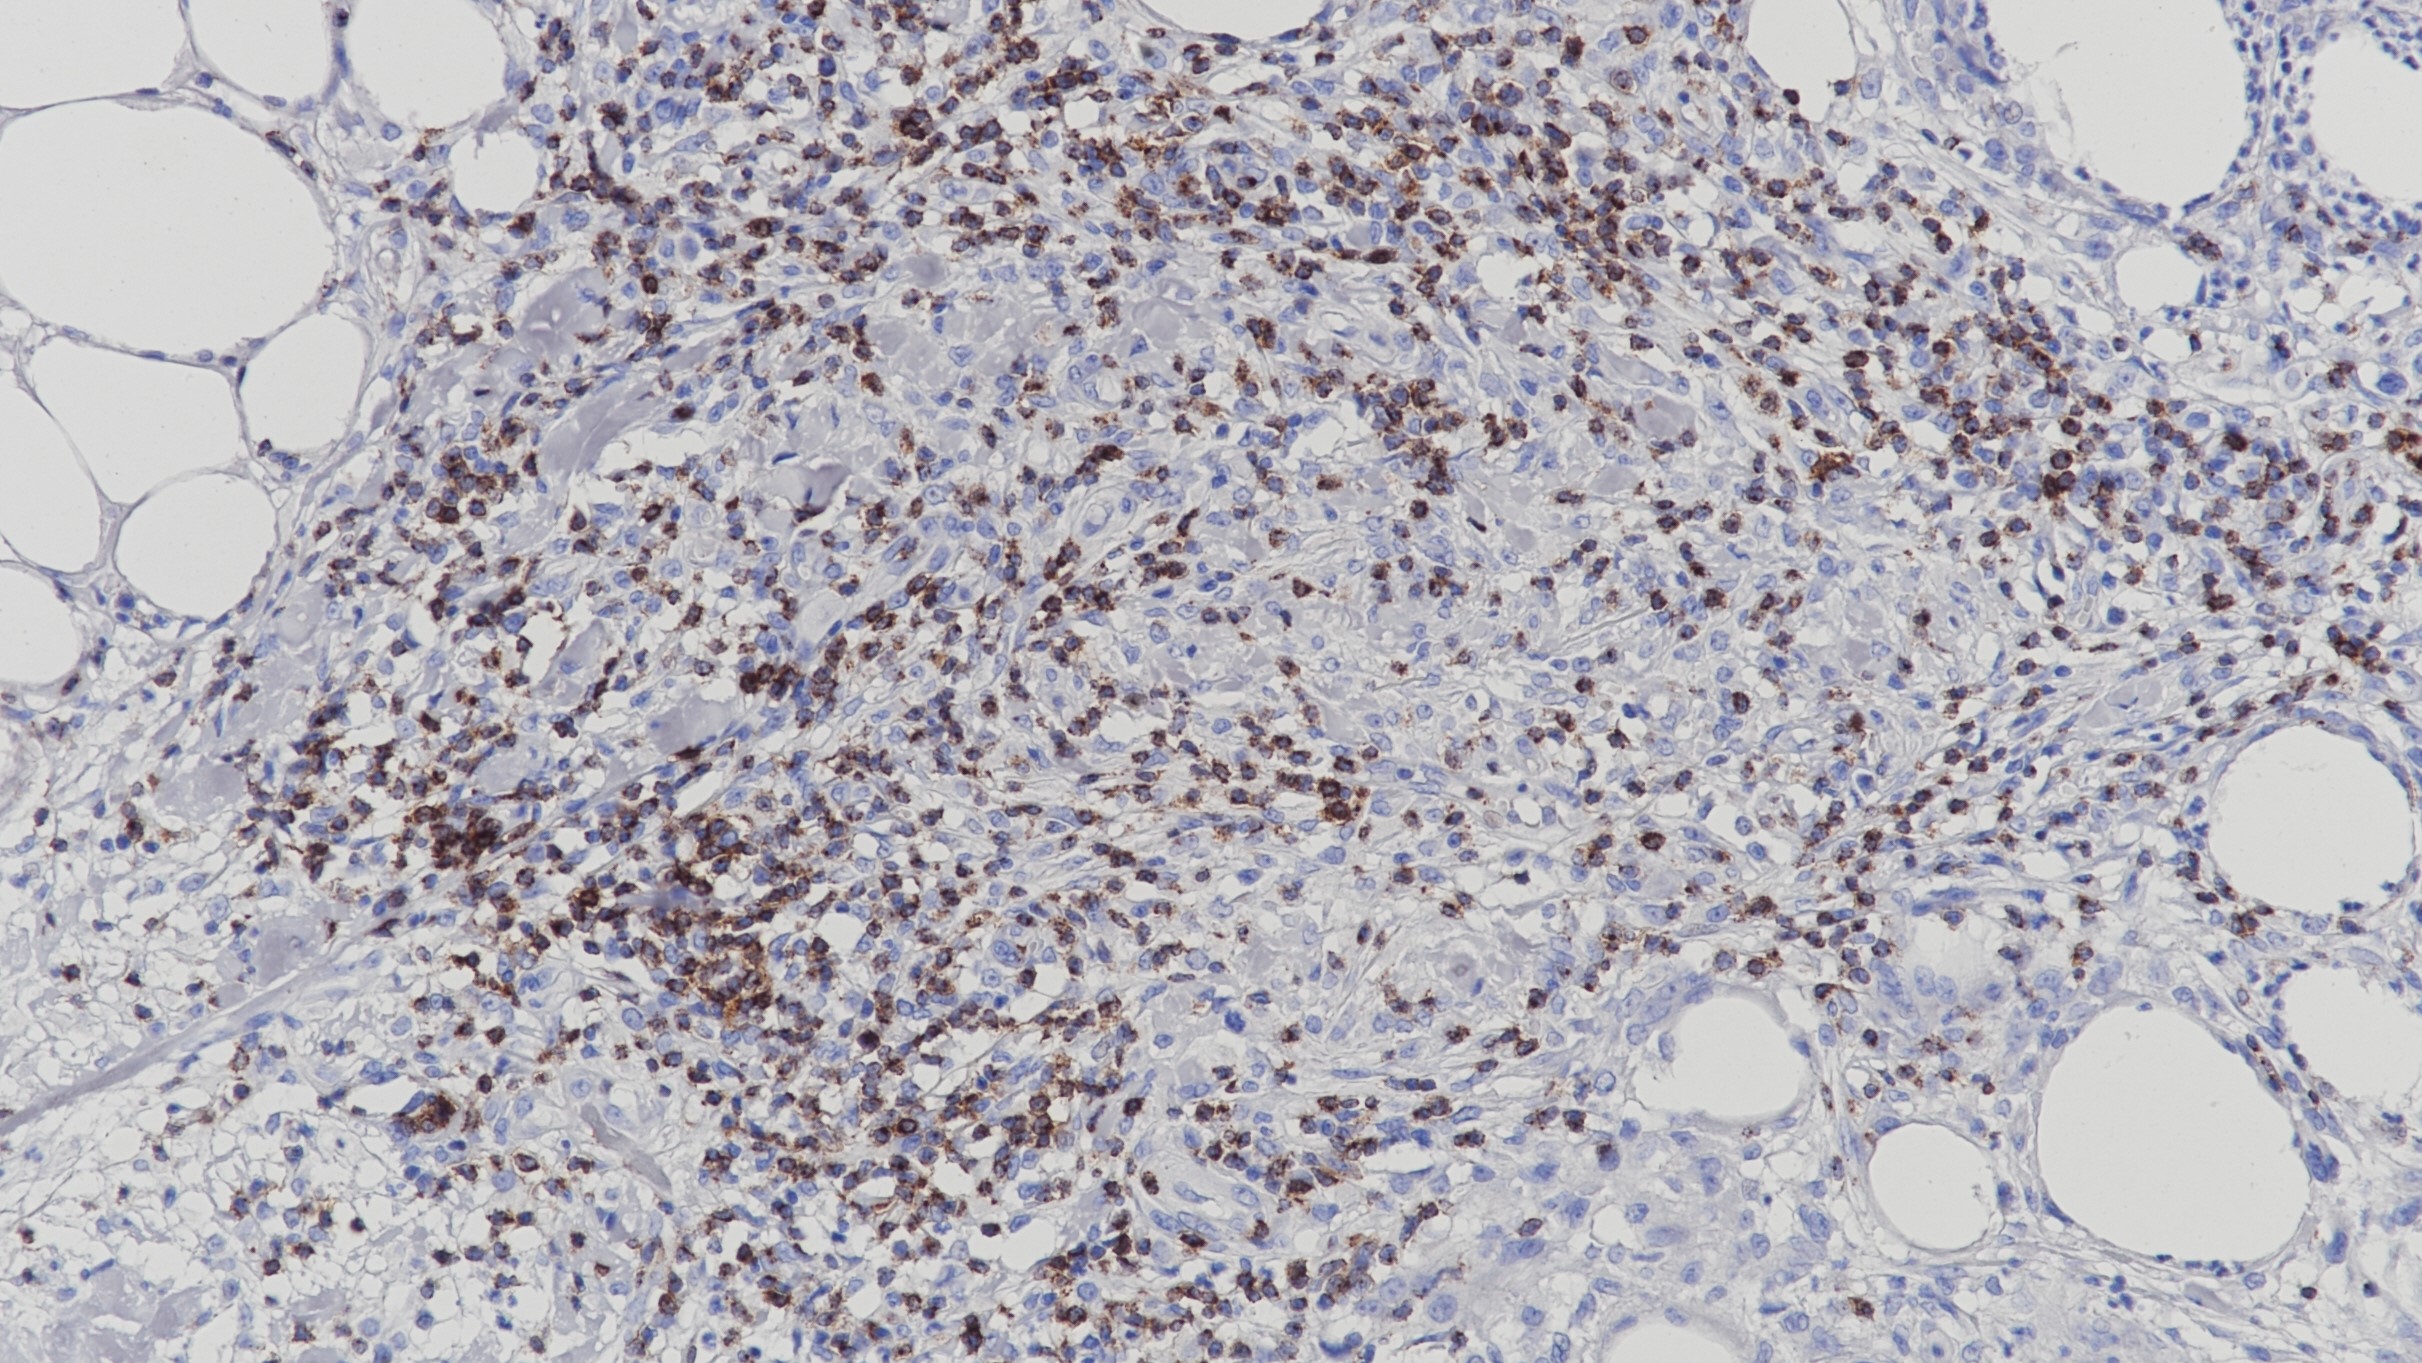

1.Regauer S, et al. CK17 and p16 expression patterns distinguish (atypical) immature squamous metaplasia from high-grade cervical intraepithelial neoplasia (CIN III). Histopathology. 2007; 50:629-35.

2.Martens JE, et al. Cytokeratin 17 and p63 are markers of the HPV target cell, the cervical stem cell. Anticancer Res. 2004; 24:771-5.